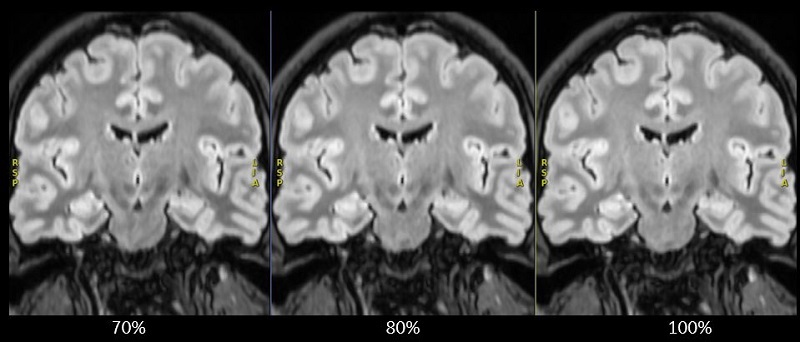

Slice Partial Fourier

Use the Slice Partial Fourier to shorten the scan acquisition time for 3D acquisitions.

The range is between 70-100%. The lower the percentage, the shorter the scan time with the tradeoff of a slight decrease in image resolution.

Figure 1. Slice Partial Fourier reformatted coronal images